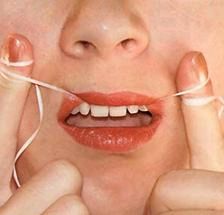

Стоматологи рекомендують користуватися зубною ниткою

Величезна увага приділяється профілактиці зубного карієсу, завдяки якій можливо уникнути його появи, або хоча б знизити шанси.

Для того, щоб уникнути карієсу, потрібно всього лише:

- Регулярно і якісно чистити зуби, бажано хорошою пастою

- Намагатися уникати перекусів, особливо солодким

- Відвідувати стоматолога не рідше одного разу на рік для профілактичного огляду, а також для видалення каменів і нальоту

Карієс між зубами - проблема дуже делікатна, а затьмарюється вона тим, що люди тягнуть до останнього з походом до стоматолога. Якщо ви хочете мати здорові зуби, то необхідно за ними доглядати.